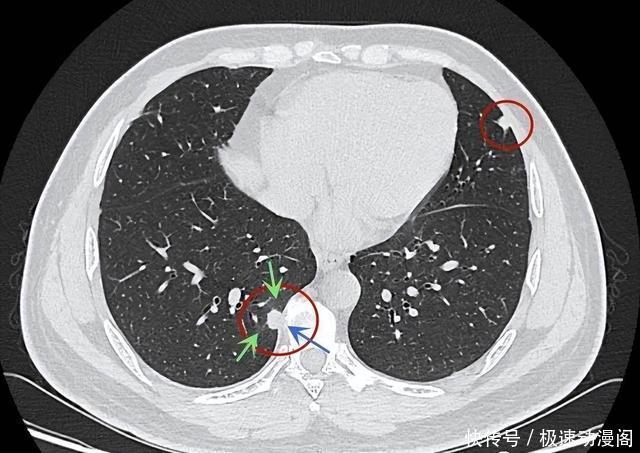

对于许多人来说,肺结石或肺结节的概念仍然比较模糊。在影像学中,肺结节是指通过胸片或CT检查在肺部发现的直径小于3cm的阴影,这些阴影可以是单个的,也可以是多个的。

在CT等影像检查中,如果发现有毛刺征、棘突征、胸膜凹陷征、血管集束征、引流线征等改变,这些都是结节可能恶化的信号,需要及时进行更深入的检查和确诊。在各类结节中,混合磨玻璃结节的恶变几率最高,其次是磨玻璃结节和实性结节。